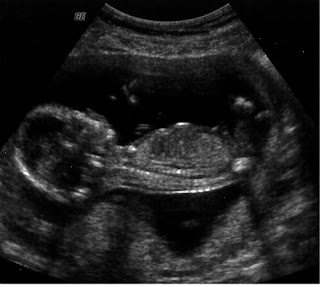

And of course, the ultrasound tech gave us a beautiful picture of the "goods."

Yup.... it's a boy! We are very excited that Grant's going to get a little brother to play with and torture!!!